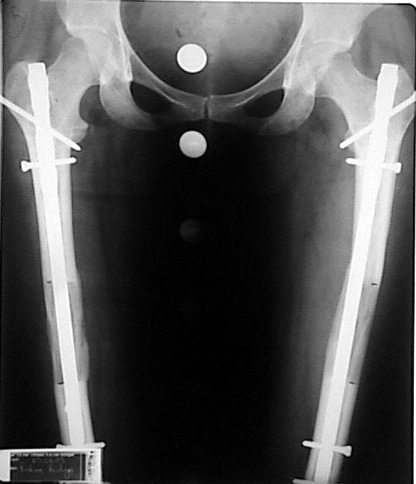

İntramedüller çivinin yerleştirilmesi ve osteotomi: Hasta traksiyon masasına supin pozisyonda yatırılır ve sağlam bacak altta olacak şekilde bacaklar makas pozisyonuna alınır. Standart yolla piriformis çukurundan medulla içine girilir ve kılavuz tel üzerinden kullanılacak çividen 1.5 mm daha kalın oyucu ile medulla oyulur. Proksimal femur, çivinin proksimali daha kalın olduğu için daha kalın oyulur. Radyografide osteotomi hattı planlaması yapılır. Planlama yapılırken uzatma sonunda distalde en az 8 cm. çivi kalması stabilizasyon için gereklidir. Kortikotomi perkütan olarak kortikotom ile tamamlanır. Daha sonra kılavuz tel çivinin boyunu ölçmek için distale ilerletilir. Uygun boyda intramedüller çivi çakılır. Son olarak çivi proksimalden kilitlenir ve bir adet dren konarak ameliyatın birinci kısmı tamamlanır.

Eksternal fiksatör uygulanımı: İntramedüller çiviye değmeden aşağıya ve yukarıya üçer adet Schanz vidası gönderilir. Vidalarla çivi arasında en az 1 mm den fazla mesafe olmalıdır.

Biz son zamanlarda, seçilmiş vakalarda, uzatma sonrası uzunluğu ve “alignment’ı” korumak amacı ile unilateral dinamik aksiyel fiksatör ve kilitli intramedüller çivi kombinasyonunu tercih etmekteyiz. Bu yöntemin ön şartları medullanın en dar çapının 7 mm.’den geniş olması ve uzatma sonrası distalde en az 8 cm. uzunluğunda çivi kalabilmesidir. İntramedüller çivi hem uzatma esnasında femurun üzerine gelen makaslama ve bükülme kuvvetlerini nötralize etmekte hem eksternal fiksasyon süresini kısaltmakta, hem de yeni oluşan kemiği kırıklara karşı korumaktadır. Serimizde bir vakada subtrokanterik femoral osteotomi yapılmıştır. İntramedüller çiviye rağmen varus angulasyonu oluşması yönünde bir dezavantaj tespit etmedik.

İntramedüller çivi ve eksternal dinamik aksiyel fiksatör kombinasyonu teknik olarak standart İlizarov uygulamalarından daha zordur. Ancak şu avantajlar yöntemi cazip hale getirmektedir; eksternal fiksasyon süresinde kısalma, refraktüre karşı korunma, erken rehabilitasyon, azami hareket genişliği kazanma ve günlük yaşam konforu. Bu avantajlar artan maliyet , artan kan kaybı ve potansiyel derin infeksiyon gibi dezavantajların önüne geçmektedir. Sonuç olarak, bulgularımızın eşliğinde, intramedüller çivi üzerinden femoral uzatma tekniğinin güvenilir ve dayanıklı bir metod olduğunu ve bizce standart İlizarov uygulamalarına üstünlük sağlayan avantajlar getirdiğini söyleyebiliriz.